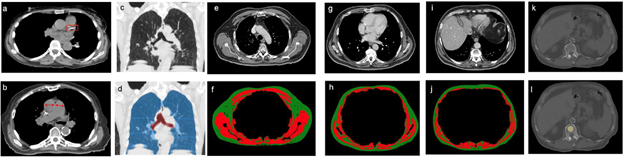

Fintelmann and team’s retrospective study included 282 patients (168 female, 114 male; median age, 75 years) with stage I lung cancer treated with SBRT between January 2009 and June 2017. To quantify CAC score and PA-to-aorta ratio, as well as emphysema and body composition, pretreatment chest CT was used. Associations of clinical and imaging features with overall were quantified using a multivariable Cox proportional hazards (PH) model.

For stage I lung cancer patients treated with SBRT, CAC score, PA-to-aorta ratio, and skeletal muscle index showed significant independent associations with overall survival. (p<.05). The model including clinical and imaging features demonstrated better discriminatory ability for 5-year overall survival than the model including clinical features alone (AUC 0.75 vs. 0.61, p<.01).

“The PA-to-aorta ratio, which is readily quantifiable with electronic calipers during routine image review, was the most important predictor of overall survival,” the authors of this AJR article concluded.